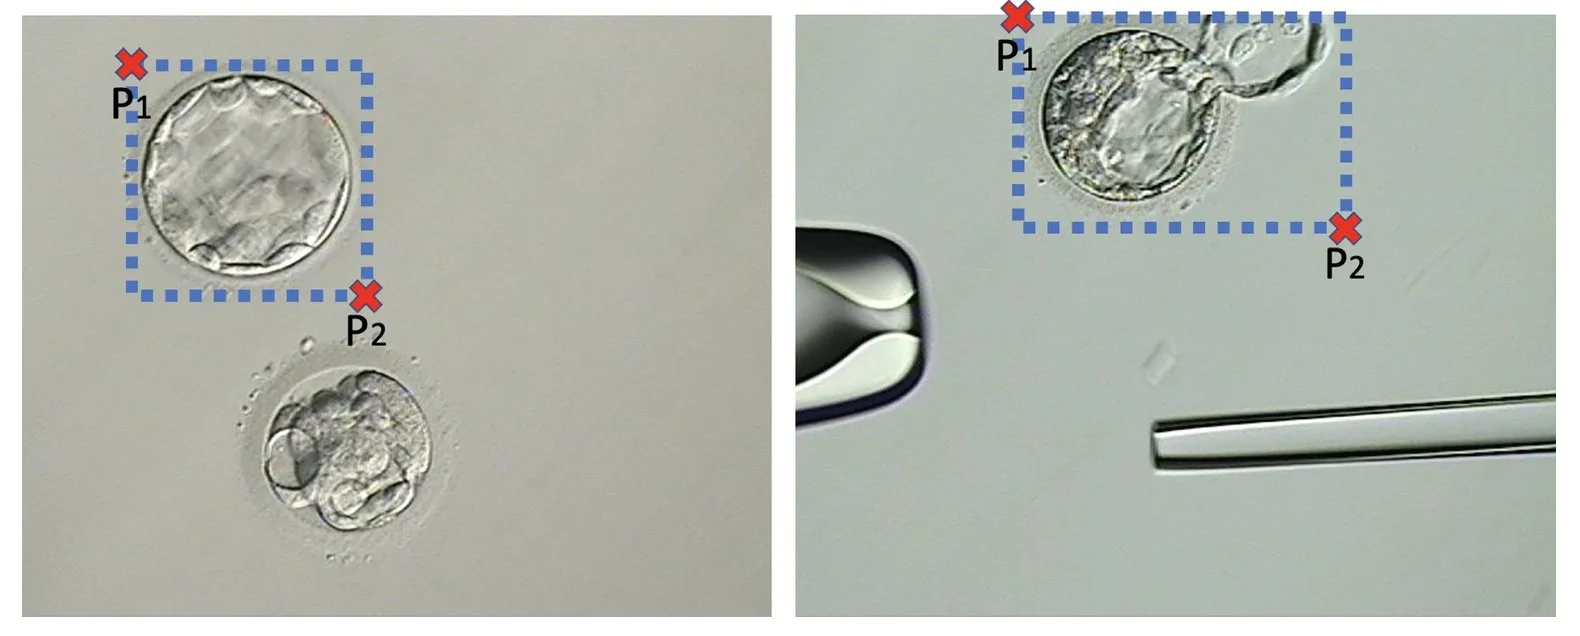

For this procedure, we employed a python implementation to detect objects using a deep neural network architecture named“retinanet”25,26 (available at: https://github.com/fizyr/keras-retinanet). This network model is trained using a dataset of micrograph images where an expert has manually annotated two points P₁ = (x₁, y₁) and P₂ = (x₂, y₂) defining the best bounding box that contains the blastocyst of interest (Fig. 5). We employed a transfer learning approach27 to train the retinanet, which initializes the weights of the model with those obtained from the training with the ‘imagenet’database28. Then the network training was performed using our blastocyst micrograph database for 50 epochs of 1,000 steps each. These parameters were manually set ensuring that the epochs vs. accuracy/loss (learning) graph reach a plateau.

Figure 5 Examples of two blastocyst micrographs and the bounding pox defined by and .

After training, the network model was capable of automatically defining the best bounding box for any input image containing a blastocyst. Using these values, we can automatically crop the original image to obtain an image O with the blastocyst centrally located and contained within the minimum area (smallest possible rectangle).